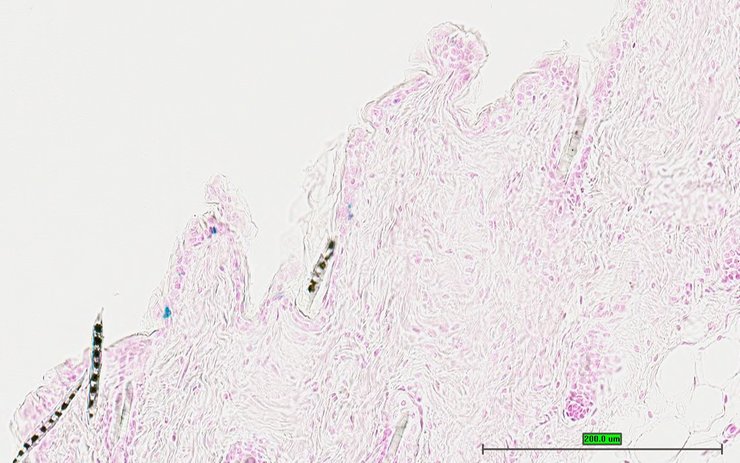

TS28: skin Present UC Davis_1883590

Specimen UC Davis_1883590: postnatal adult; Prf1tm1.1(KOMP)Vlcg/Prf1+ (more )